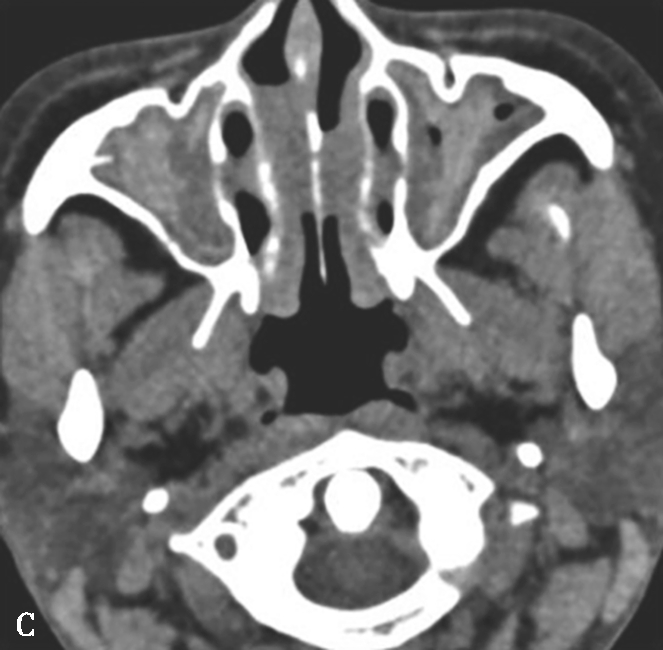

图1-3-21 真菌球

A~C.横断面CT骨窗、横断面软组织窗、冠状面CT骨窗,A、C示左侧上颌窦内充填软组织密度影,伴中央多发条状、云絮状高密度影,上颌窦窦口扩大,窦壁骨质增生硬化、肥厚;B示窦腔实变,中央高密度影显示更清楚;D~F.MRI横断面T 1 WI、T 2 WI及增强T 1 WI,示左侧上颌窦内软组织影,T 1 WI呈等、高信号,T 2 WI呈等、高信号,窦口区病变T 1 WI呈不规则形等、稍高信号,T 2 WI呈极低信号,增强扫描后窦口区病变无强化,周边黏膜呈线样强化